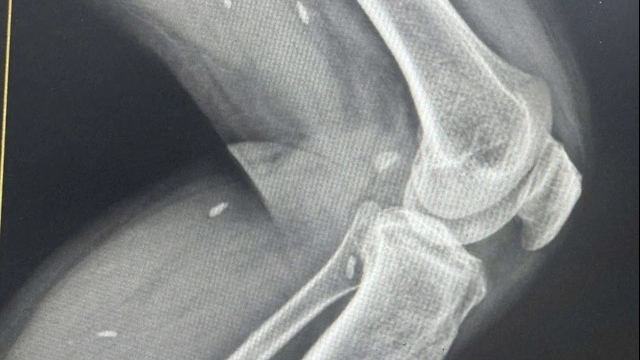

| Trào lưu nguy hiểm thêm hàn the v ào nước uống để giảm viêm, đau khớp (Ảnh: Getty) |